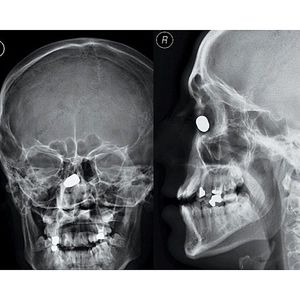

Bullet-proof nose?!

This poor guy was shot in the face at close range, but his nose stopped the bullet, saving his life.